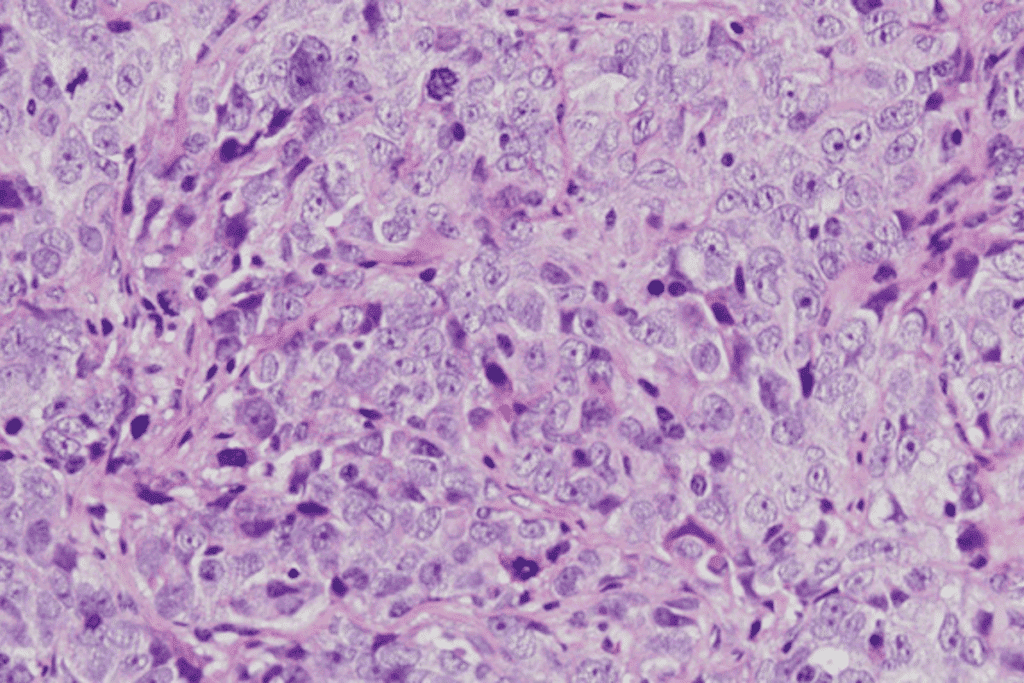

Cellular Composition of Solid Tumors

Solid tumors are made up of different cell types. Each cell type plays a role in how the tumor grows and reacts to treatment. Understanding these cells is key to fighting cancer.

Tissue Origins and Cell Types

Solid tumors come from various tissues like epithelial, connective, and muscular. The cells in a tumor show traits from where it started. For example, carcinomas, which start from epithelial cells, are common and can be classified further.

These tumors are complex because they have many cell types. This includes cancer cells and non-cancer cells like immune cells and fibroblasts. This mix affects how the tumor grows and how it responds to treatment.

Structural Organization Within Solid Tumors

The way cells are arranged in solid tumors affects its behavior. Tumors with a disorganized structure tend to grow faster and be more aggressive. This makes them harder to treat.

The tumor microenvironment, with its cells and matrix, shapes the tumor’s structure. Things like hypoxia, angiogenesis, and immune cells play a big role in this. They help create the tumor’s complex layout.